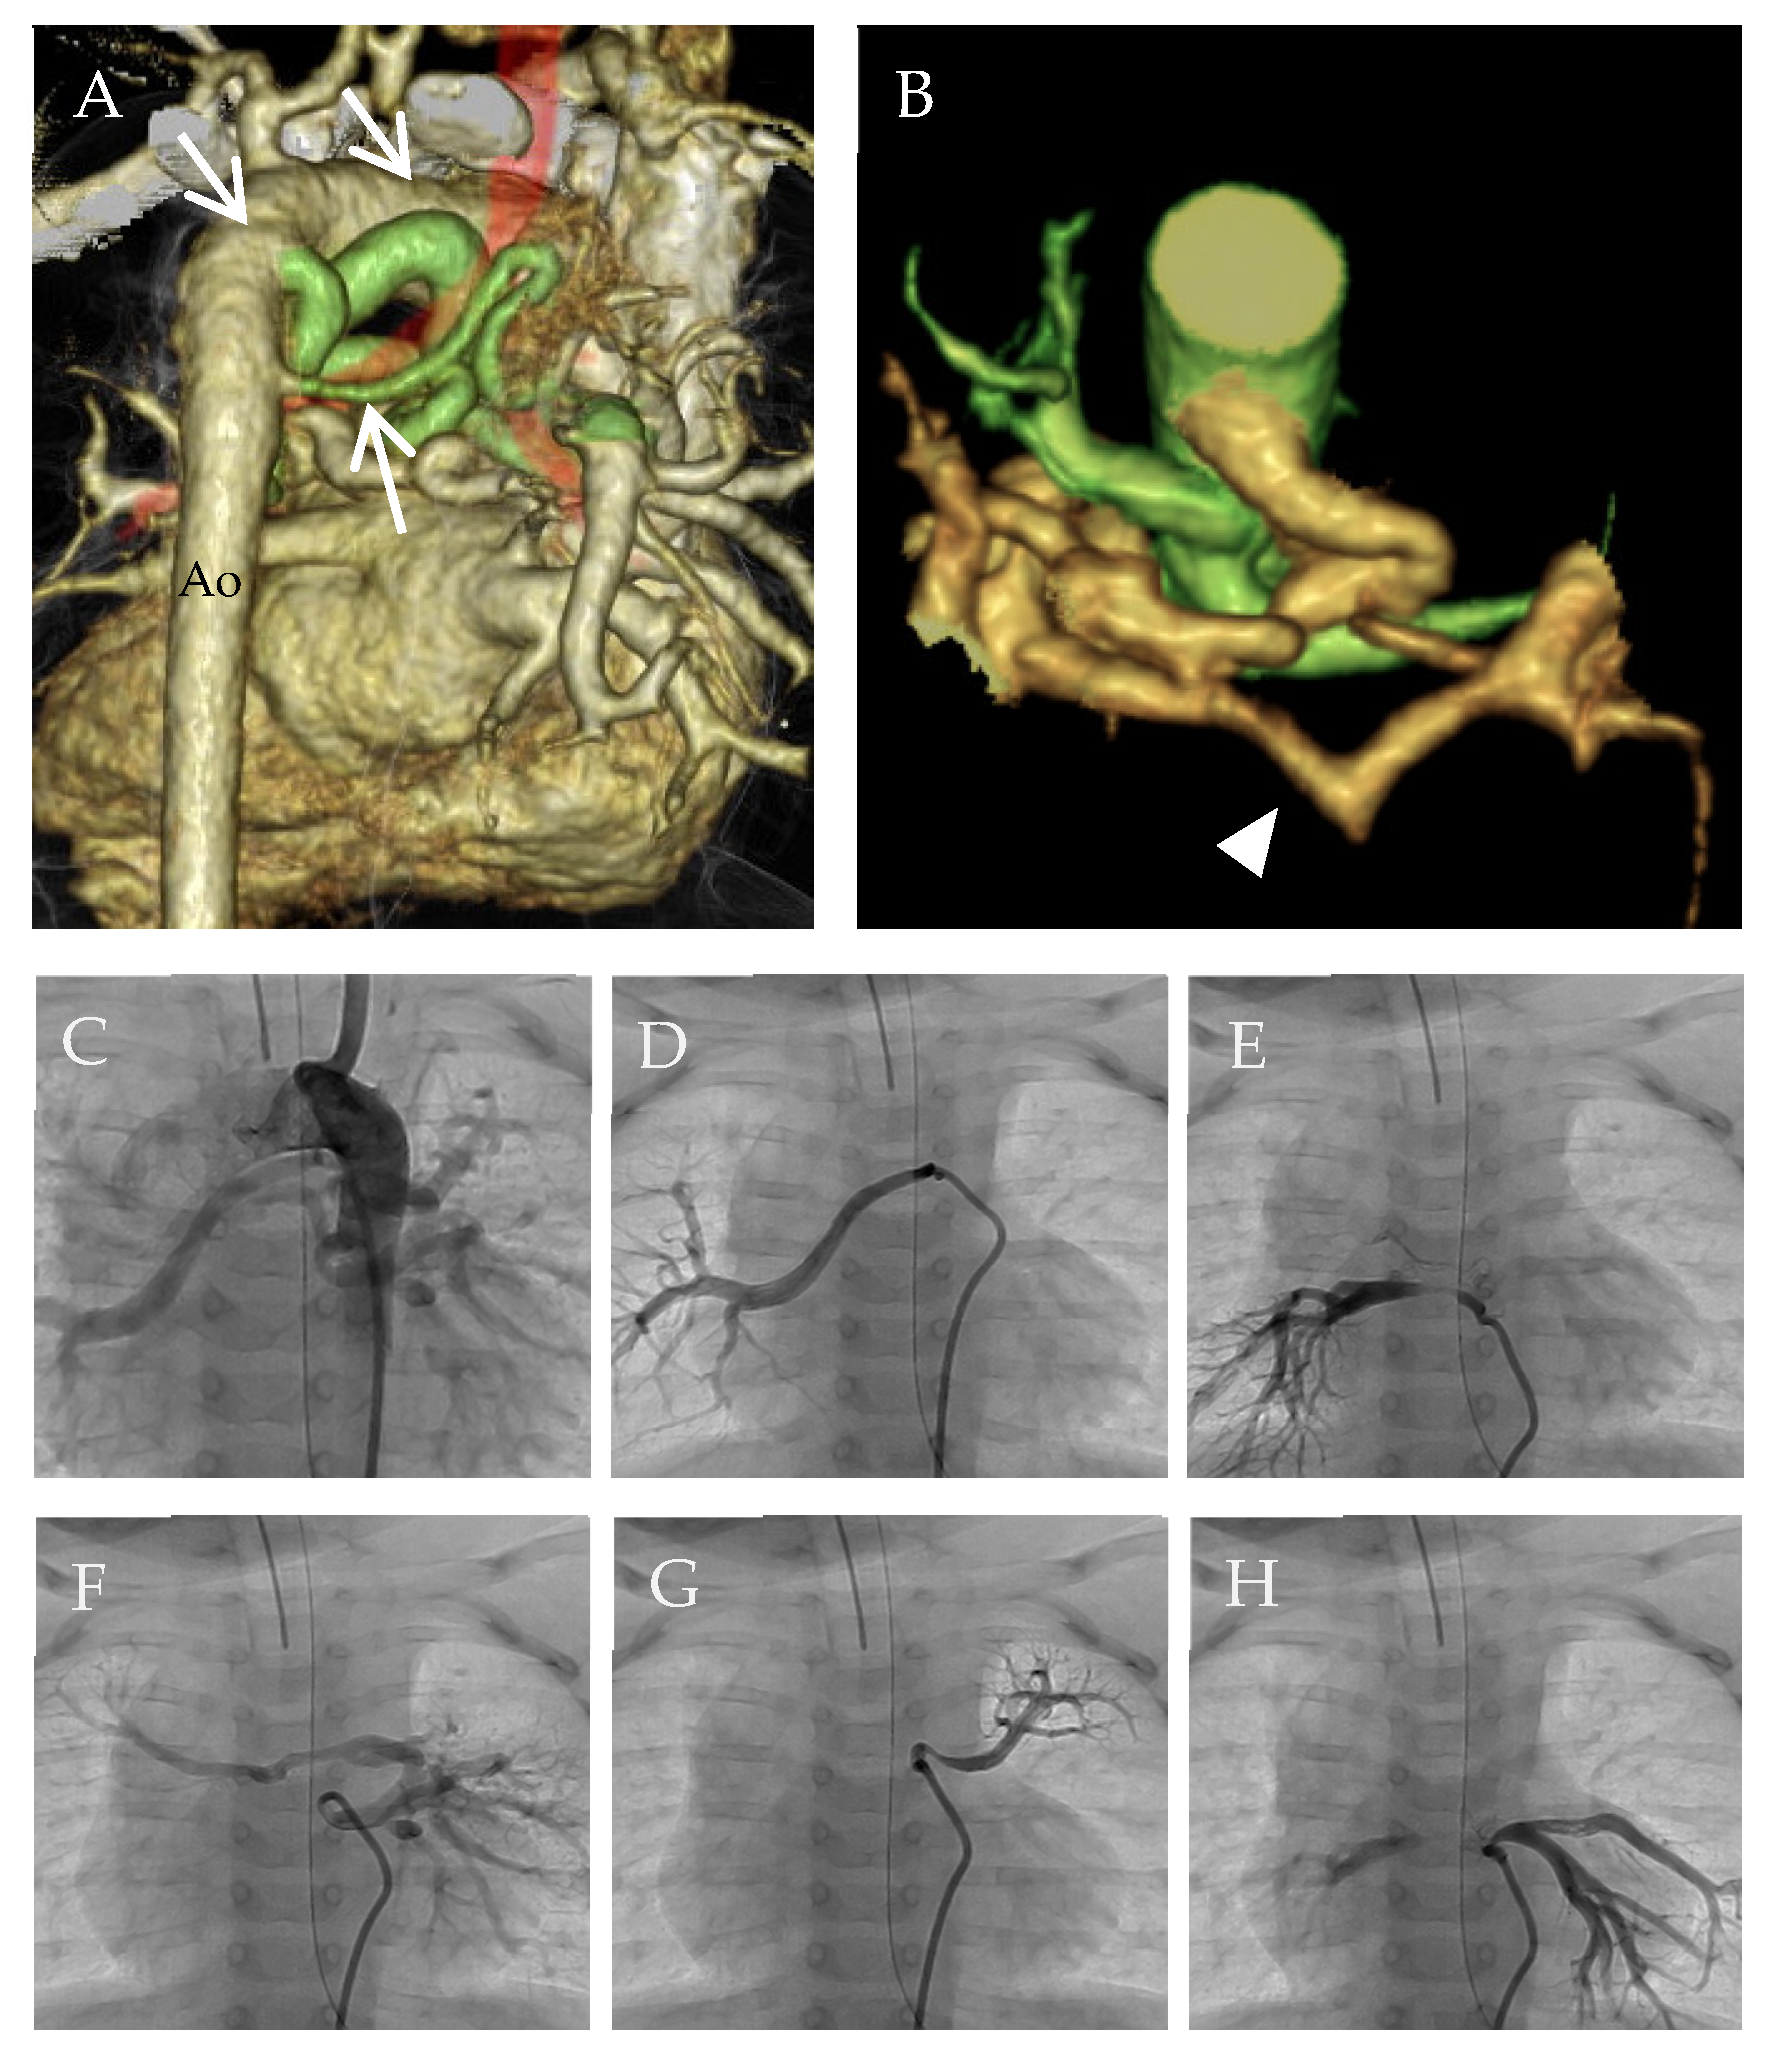

2.2. Segmental PH Associated with MAPCAs

2.3. Surgical Treatment for MAPCAs to Avoid Segmental PH